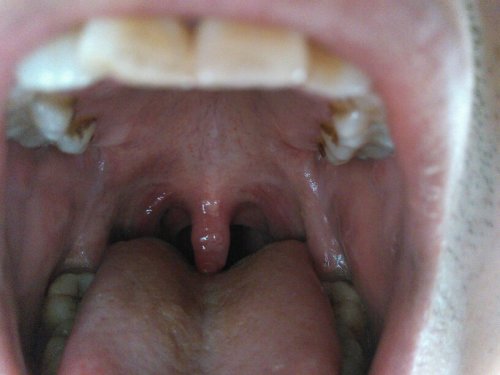

嗓子感覺糊了一層粘液,原因、緩解與預(yù)防策略,嗓子糊粘液,成因、緩解及預(yù)防策略

摘要:嗓子感覺糊了一層粘液可能是由于多種原因引起的,如感冒、過敏或慢性喉炎等。為了緩解這種癥狀,可以嘗試多喝水、避免過度用嗓和保持室內(nèi)空氣濕度。預(yù)防策略包括保持良好的生活習(xí)慣,增強(qiáng)免疫力,避免接觸過敏源等。如有持續(xù)不...